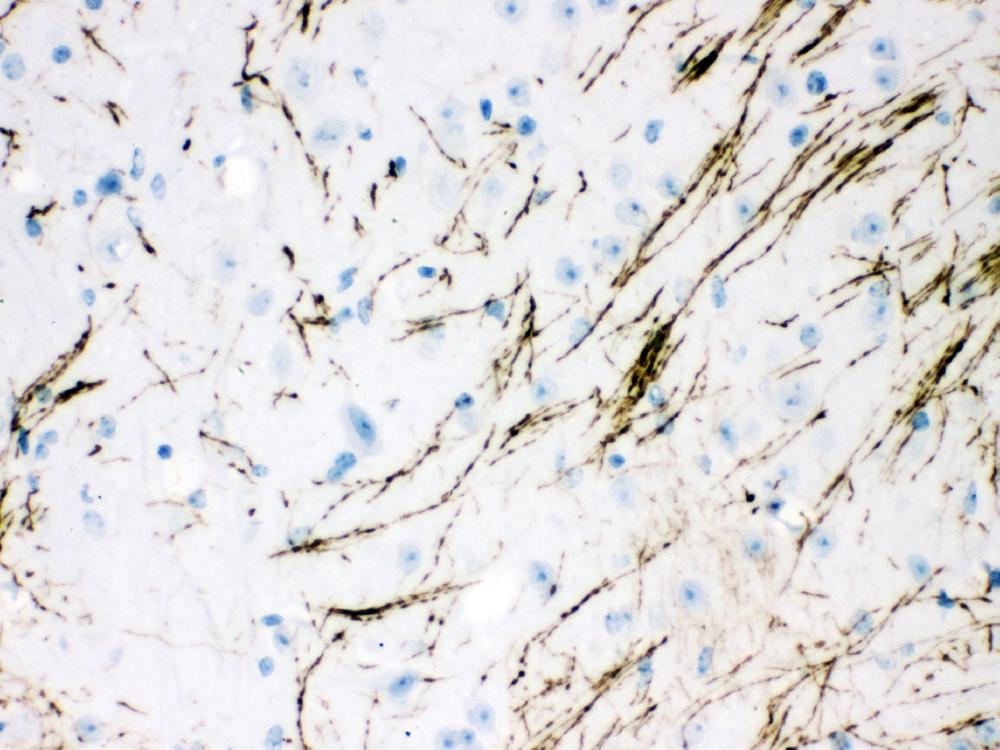

IHC analysis of TH using anti-TH antibody (PB9449).

TH was detected in a paraffin-embedded section of human brain tissue. Biotinylated goat anti-rabbit IgG was used as secondary antibody. The tissue section was incubated with rabbit anti-TH Antibody (PB9449) at a dilution of 1:200 and developed using Strepavidin-Biotin-Complex (SABC) (Catalog # SA1022) with DAB (Catalog # AR1027) as the chromogen.